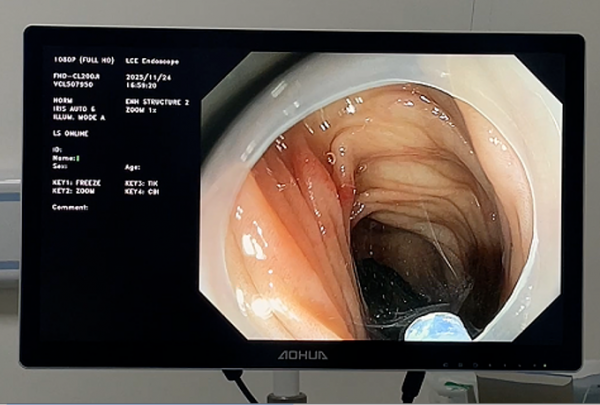

术中,张俊伟主任凭借娴熟的操作技巧,在胃镜直视下精准定位钢笔帽,利用网篮轻柔包裹异物,缓慢将其拖出。整个手术过程仅耗时15分钟,异物完整取出,患儿生命体征平稳,未出现任何不良反应。

胃镜高清成像可清晰观察异物位置及周围组织,减少误伤风险。